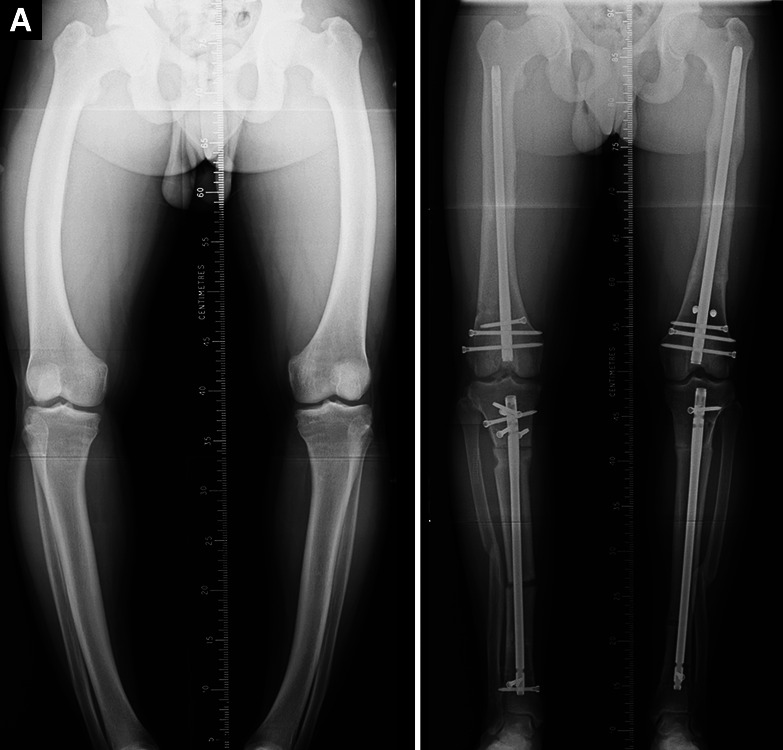

Introduction: Computerised hexapod-assisted orthopaedic surgery (CHAOS) is a method by which complex multiplanar, multilevel deformity can be corrected with a high degree of accuracy utilising minimally invasive techniques within a single operative event. This study's aim was to report the reliability, accuracy and magnitude of correction achieved, alongside patient-reported outcomes and risk factors for complications when using the CHAOS technique throughout the lower limb.

Materials and methods: Retrospective review of medical records and radiographs for consecutive patients who underwent CHAOS for lower limb deformity correction at a tertiary centre between 2012 and 2020.

Results: There were 70 cases in 56 patients, with the site of surgery being the femur in 48 cases, proximal tibia in 17 and distal tibia in 5 cases. Multiplanar correction was performed in 43 cases, and multilevel osteotomy was undertaken in 23 cases. Fixation was undertaken with intramedullary nailing (IMN) in 49 cases and locked plates in 21.The maximum corrections were 40° rotation, 20° coronal angulation, 51° sagittal angulation and 62-mm mechanical axis deviation (MAD). Deformity correction was mechanically satisfactory in all patients bar one who was undercorrected requiring revision. The mean patient global impression of change (PGIC) score was 6.2 out of 7.Overall complication rate was 12/70 (17%). Complications from femoral surgery included two nonunions, one case of undercorrection, one case of stiffness, one muscle hernia and one pulmonary embolism. Complications from tibial surgery were one compartment syndrome, one pseudoaneurysm of the anterior tibial artery requiring stenting, one transient neurapraxia of the common peroneal nerve, one locking plate fatigue failure, one seroma and one superficial wound infection.

Conclusion: Computerised hexapod-assisted orthopaedic surgery can be used for accurate correction of complex multilevel and multiplanar deformities of both the femur and tibia. The risk profile appears to differ between femoral and tibial surgeries, and also to that of traditional circular frame correction. Patients remain highly satisfied with both the functional and symptomatic outcomes.